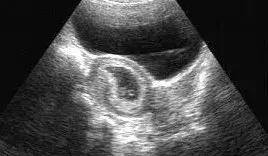

B超就是利用超声波了解体内结构的一种观察仪器。原理说白了很简单,就是发射超声波,超声波也是声音的一种,具有穿透能力,并且和所有的声音一样,遇到屏障会产生回声,不同的屏障回声的方式也不同,于是利用电脑收集这些回声,转化为相应的图像在屏幕上显示出来,起到观察内部脏器等作用。

彩超和B超的主要区别可不是像彩电和黑白电视机那样简单。彩超的主要技术指标如(探头晶片数、成像通道数、成像动态范围、主机处理能力和深度等方面)均大大高于B超。

因此能够显著提高图像分辨率,可以更早期发现更细小的病变,提高疾病的早期诊断率,并可更清晰地显示病灶周边和内部变化的细节,提高诊断的准确性。

彩超具有彩色多普勒血流显像功能,可以显示病变区域的血管解剖结构、血流方向、血流速度和血流状态改变,可以明显提高对疾病的鉴别能力,提高诊断的准确性。

彩超具有组织谐波成像功能,可以明显降低因肥胖、气体和其它伪像干扰,提高图像清晰度。因此,彩超检查能够更早期地发现病变,并能够更加准确地对病变进行鉴别诊断,明显提高诊断的准确率,而B超检查的漏诊率和误诊率则明显高于彩超。